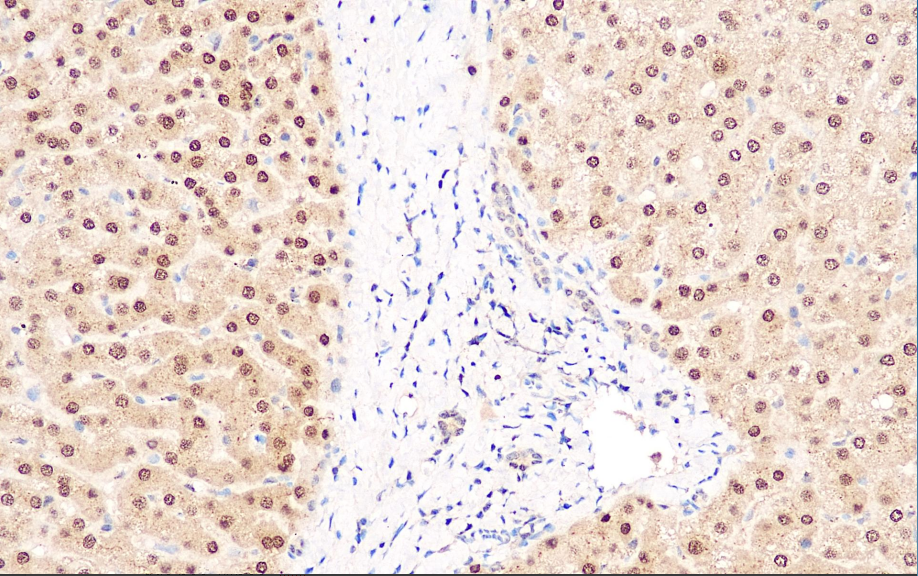

Positive Control: Liver

MGMT(O6-methylguanine-DNA-methyltransferase) is a DNA repair enzyme with a molecular weight of 25kDa. The mechanism of action of alkylating agents of tumor chemotherapy drugs (such as BCNU, CCNU, DTIC, Procarbazine, Temozolomide, etc.) is to form lethal cross-links at the O6 position of guanine in DNA. MGMT can transfer alkyl groups from the guanine O6 position of DNA to cysteine residues, thereby restoring the complete structure of DNA. This transfer causes the loss of MGMT enzyme activity, so the MGMT level in cells is closely related to the DNA damage they can tolerate. Generally speaking, tumors with low expression of MGMT can be treated with the above-mentioned chemotherapy drugs. Conversely, it is drug resistance. It is highly expressed in the liver in normal tissues; Low-level expression in brain tissue and bone marrow.

The MGMT antibody reagent can specifically bind to MGMT antigen. The immunohistochemical kit containing MGMT antibody reagent is suitable for prognosis assessment and treatment prediction of glioma and colorectal cancer.